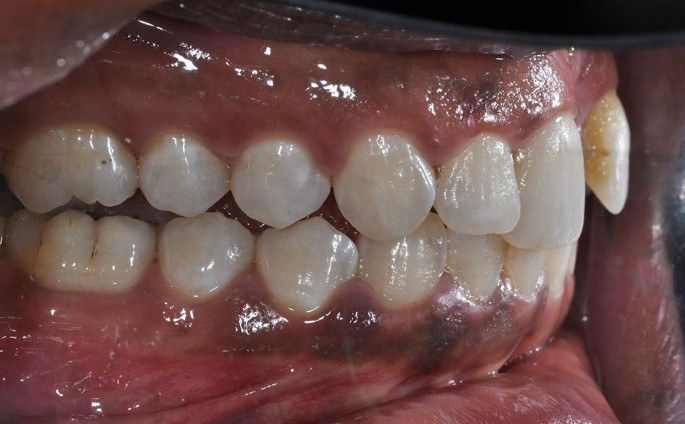

Lateral luxation of 11 and the resulting disclusion of the posterior teeth

Intrusion of a central incisor, loss of a lateral incisor and laceration of the gingivae following trauma